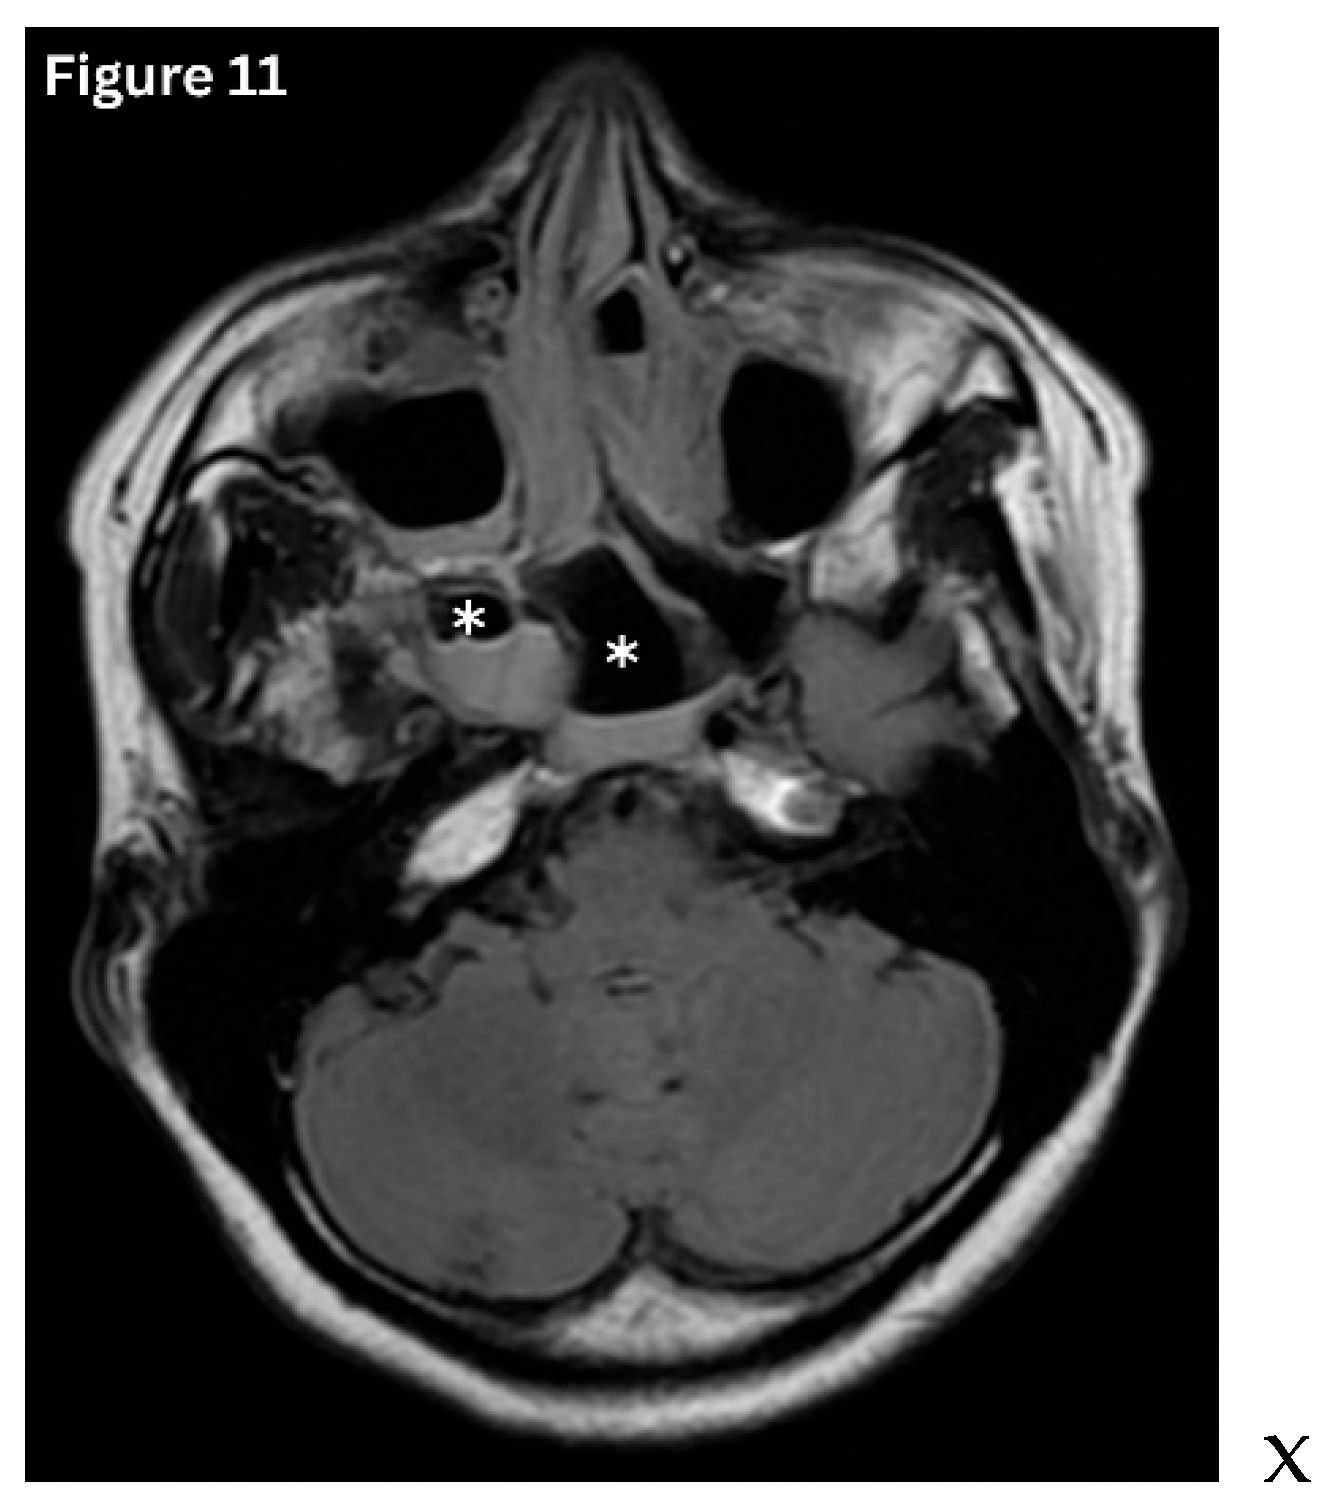

Acute sinusitis typically demonstrates air–fluid levels, diffuse mucosal thickening, and narrowing of the sinus drainage pathways on imaging. (Figure 11) Chronic sinusitis develops over several months and is characterised by persistent polypoid mucosal thickening, bony remodelling, and sclerosis of the sinus walls on sinus HRCT. (Figure 12 and Figure 13) Allergic fungal rhinosinusitis is characterised by expanded sinuses containing centrally hyperdense inspissated mucin, accompanied by a peripheral hypodense mucosal rim, often in association with nasal polyps, as seen on HRCT. Recurrent and subacute sinusitis exhibits overlapping features of both acute and chronic disease. This is often associated with partial ostial obstruction or underlying anatomical variations [5,16].

Figure 11. Axial MRI- FLAIR image shows Fluid levels in the sphenoid sinus with mucosal oedema consistent with acute sphenoid sinusitis.